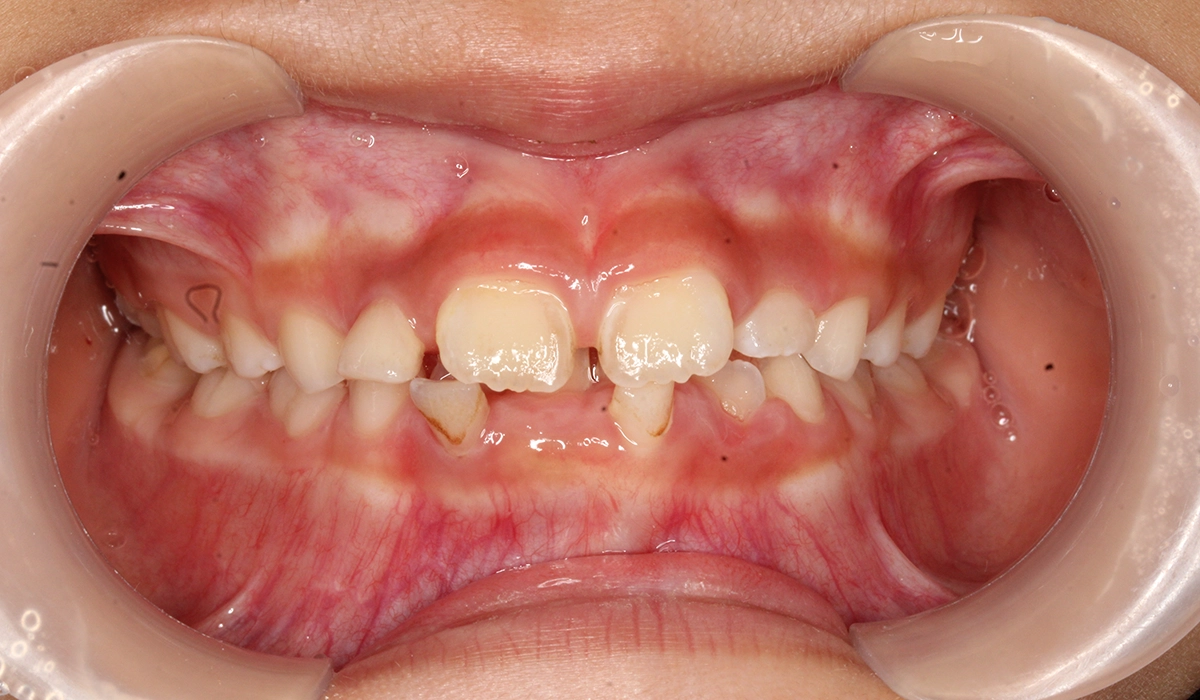

術前:正面

術後:正面